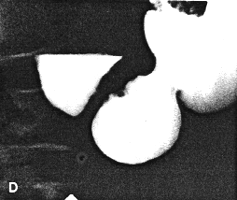

Six months later, after proper diabetic control, he had improved clinically. On this occasion the stomach contained less residual food. Shallow gastric peristaltic waves were present, while the pyloric sphincteric cylinder remained partially contracted throughout the examination (Fig. 37.1C). Although this was less marked than on the previous occasion, normal cyclical activity remained absent and no maximal or complete contractions were seen. Peristaltic activity in the duodenum appeared to be decreased. Active peristaltic contractions with a fast passage of barium was noted in the jejunum. The films also showed scattered areas of calcification in the pancreas and the case was diagnosed as diabetic gastroparesis and chronic alcoholic pancreatitis. Case 37.2. T.M., 64 year old female with longstanding insulin-dependent diabetes mellitus and psychotic symptoms, was admitted with epigastric pain and episodes of vomiting. Radiological examination showed a decrease in frequency and intensity of gastric peristaltic waves; there was a lack of cyclical contraction and relaxation of the pyloric sphincteric cylinder, which remained in a state of partial contraction throughout the examination; this was associated with a patulous pyloric orifice measuring 1.2 cm in diameter. Sonographically the gall bladder, liver, spleen, kidneys and aorta were normal. The pancreas could not be visualized owing to obesity.

| Fig. 37.1. C-F. Case D.R. After treatment and clinical improvement. Lessened contraction of sphincteric cylinder. Some movement evident but normal cyclical activity absent. Note pancreatic calcification | |